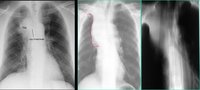

X線表現

①癌瘤局限於黏膜,未構成支氣管的狹窄及阻塞者,X線上可無陽性表現。

②癌瘤致支氣管狹窄,可出現一側或葉的肺氣腫。深呼氣位照片易於顯示。

③癌瘤致支氣管狹窄,造成分泌物引流不暢,則出現阻塞性肺炎或阻塞性肺不張。

④癌瘤致支氣管阻塞則出現阻塞性肺不張。另外,癌瘤向支氣管外蔓延,形成肺門區腫塊。右上葉肺癌可出現典型的橫“S”征。

⑤癌瘤主要向支氣管管外蔓延,在肺門區形成腫塊及結節,邊緣多呈分葉狀或欠規則。右側者可示肺門角消失。

⑥支氣管體層示支氣管壁不規則增厚,管腔局限性不規則狹窄甚至截斷。可見軟組織腫塊。

⑦支氣管造影示管腔對稱性或不規則狹窄,支氣管阻斷及杯口樣充盈缺損。